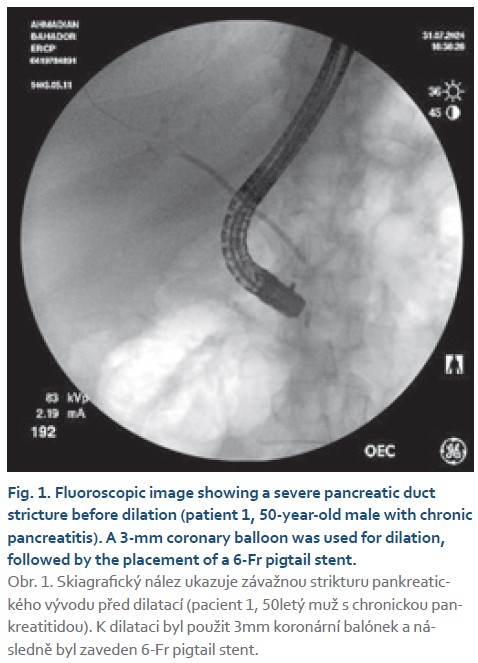

- patient 1: a tight pancreatic duct stricture was managed with a 3- mm coronary balloon, followed by a 6-Fr pigtail stent;

- patient 1: 50-year-old male with chronic pancreatitis;